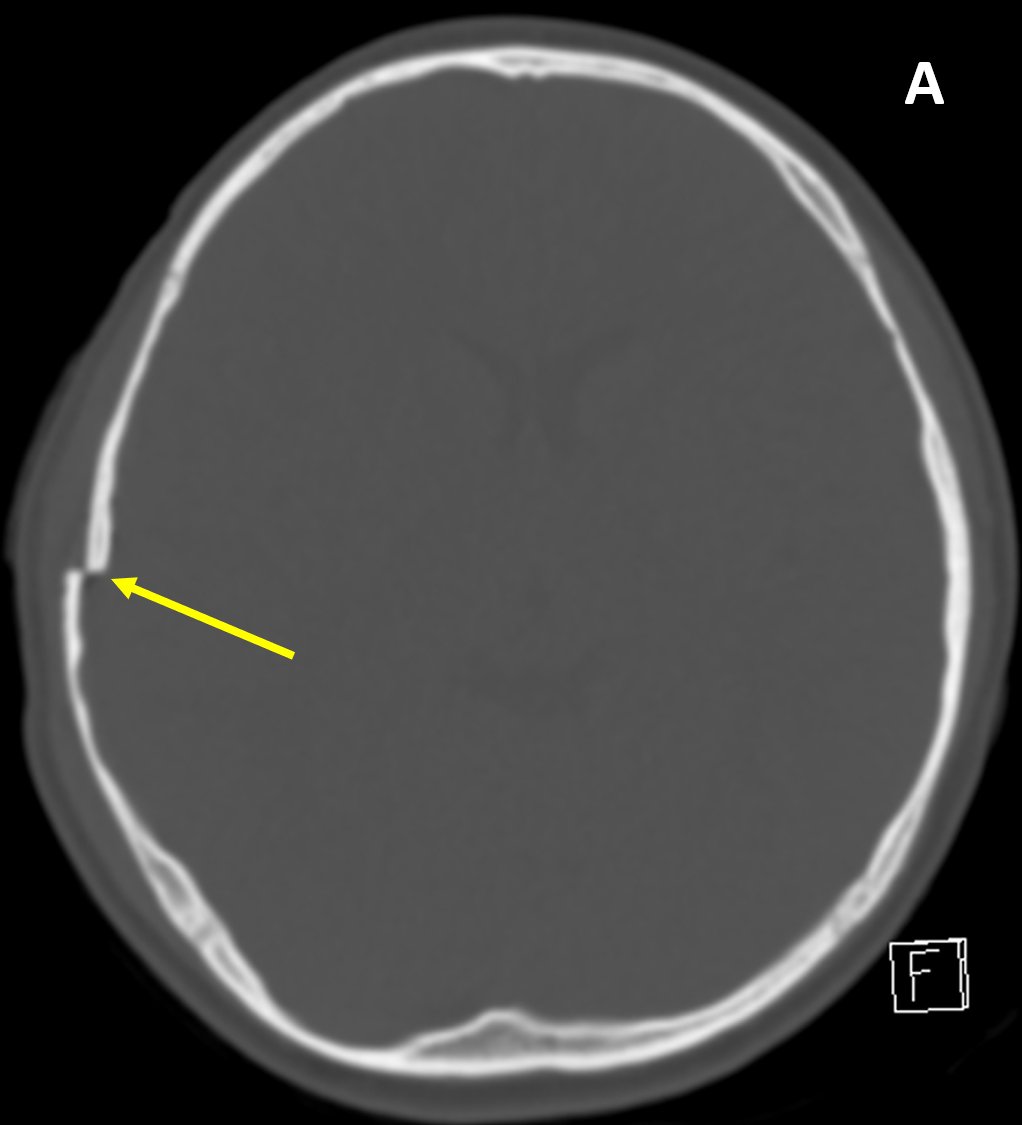

Skull Fracture - MRI Online https://hubs.ly/H0mMQZb0 by

@jannimd Fractures involving paranasal sinuses or temporal bone air cells are potential sites of intracranial communication and a route of infection, cerebrospinal fluid leak (rhinorrhea, otorrhea), or pneumocephaluspic.twitter.com/q4dDJOYKo8